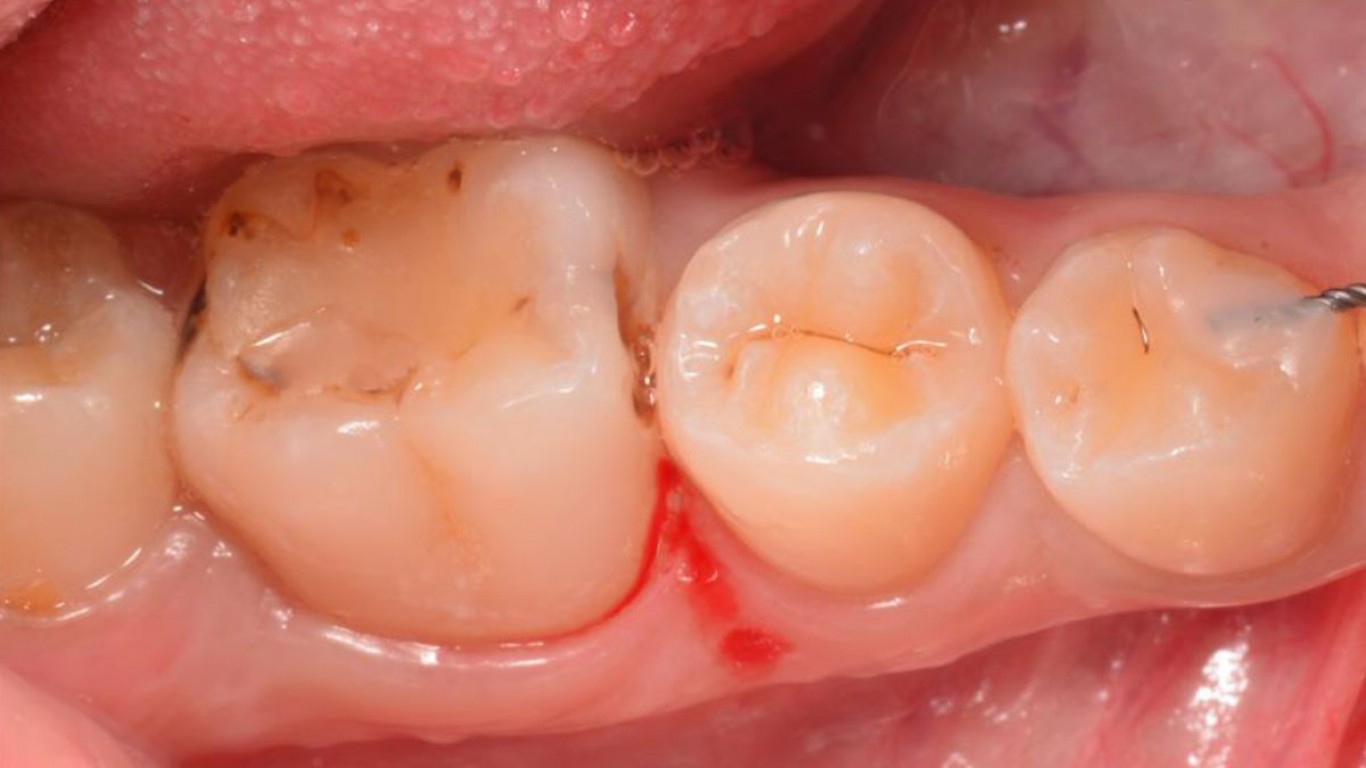

01 Inicijalnim pregledom se uočavaju stari kompozitni ispun i karijesna lezija na molaru 36.